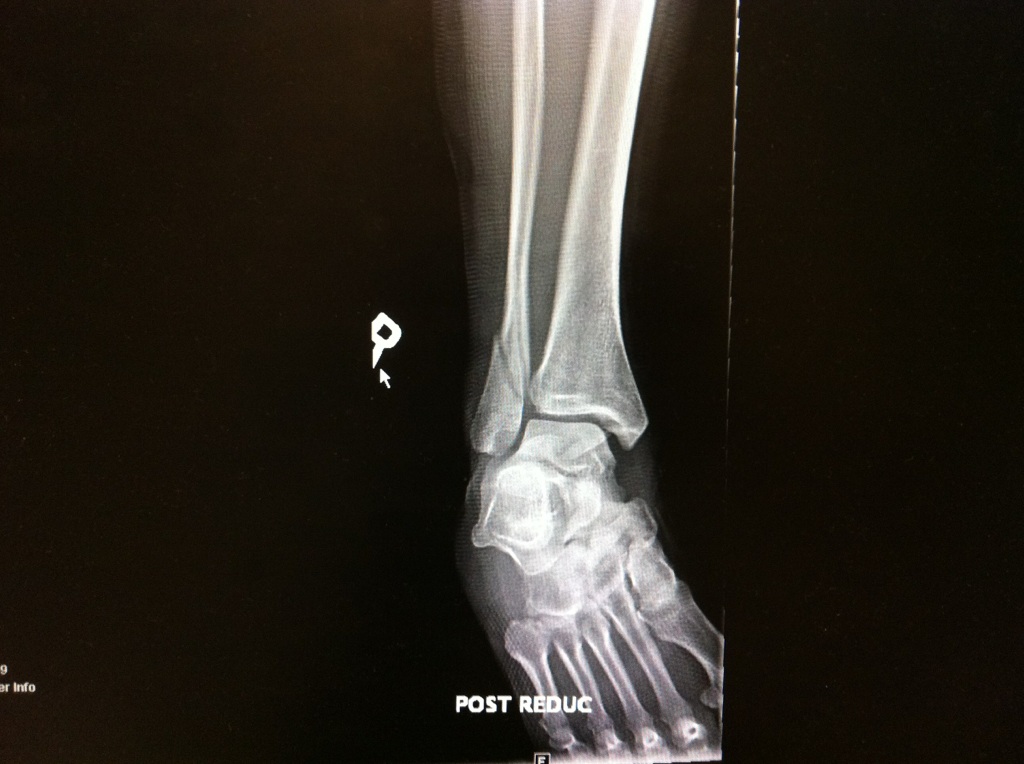

Fractured and Dislocated Ankle Stock Image C009/4783 Science Is My Ankle Dislocated — ankle dislocations usually occur due to trauma from a fall, sports injury, or motor vehicle accident. The anterior, posterior, medial and lateral dislocation can usually be reduced in a&e under sedation, while a superior dislocation requires an mdt consultation to decide on the best treatment. your ankle can be forced out of its normal position (dislocated) after. Is My Ankle Dislocated.

Fractured and dislocated ankle, Xray Stock Image C017/7976 Is My Ankle Dislocated — there are 5 directions that an ankle can dislocate: The anterior, posterior, medial and lateral dislocation can usually be reduced in a&e under sedation, while a superior dislocation requires an mdt consultation to decide on the best treatment. Anteriorly, posterior, laterally, medially or superiorly in relation to the talus bone on the tibia bone. — a dislocated. Is My Ankle Dislocated.

Dislocated ankle, Xray Stock Photo Alamy Is My Ankle Dislocated — an dislocated ankle causes symptoms such as pain, swelling, bruising, possible tingling and numbness in the foot, and ankle deformity. your ankle can be forced out of its normal position (dislocated) after an accident, in a fall, or when playing sports. Anteriorly, posterior, laterally, medially or superiorly in relation to the talus bone on the tibia bone.. Is My Ankle Dislocated.

Dislocated ankle, Xray Stock Image F034/2050 Science Photo Library Is My Ankle Dislocated — there are 5 directions that an ankle can dislocate: They are relatively rare as all the ligaments on one side of the ankle have to rupture The anterior, posterior, medial and lateral dislocation can usually be reduced in a&e under sedation, while a superior dislocation requires an mdt consultation to decide on the best treatment. — ankle. Is My Ankle Dislocated.